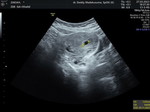

Diusia kehamilan 4 minggu apakah boleh berpuasa ramadhan